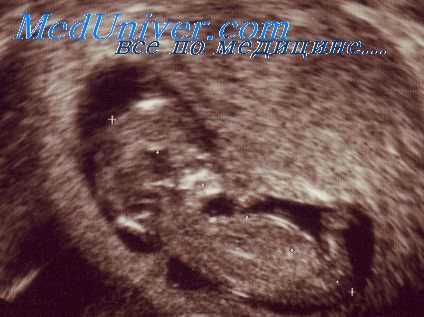

Боковые желудочки мозга имеют сложную трехмерную архитектонику, которая по мере прогрессирования беременности подвергается очень существенным изменениям. Поэтому неудивительно, что эхографическая оценка этих структур была предметом многочисленных исследований, в ходе которых было предложено много различных подходов к методам выявления и диагностики вентрикуломегалии У плода.

Были созданы нормативные таблицы для оценки размеров разных отделов боковых желудочков, которые измерялись как в стандартных поперечных (аксиальных), так и во фронтальных (коронарных) и продольных (сагиттальных) плоскостях. Тем не менее измерение поперечного диаметра преддверия (атриума) бокового желудочка на Уровне гломуса сосудистого сплетения в настоящее время является наиболее предпочтительным. В большинстве случаев, это измерение легко осуществляется и имеет высокую воспроизводимость.

По данным различных исследований были получены весьма близкие по значениям результаты при измерении во втором триместре беременности, при этом средняя ширина атриума составила приблизительно 7 мм со стандартным отклонением всего 1 мм. При измерениях в третьем триместре были получены несколько большие различия между нормальными значениями.